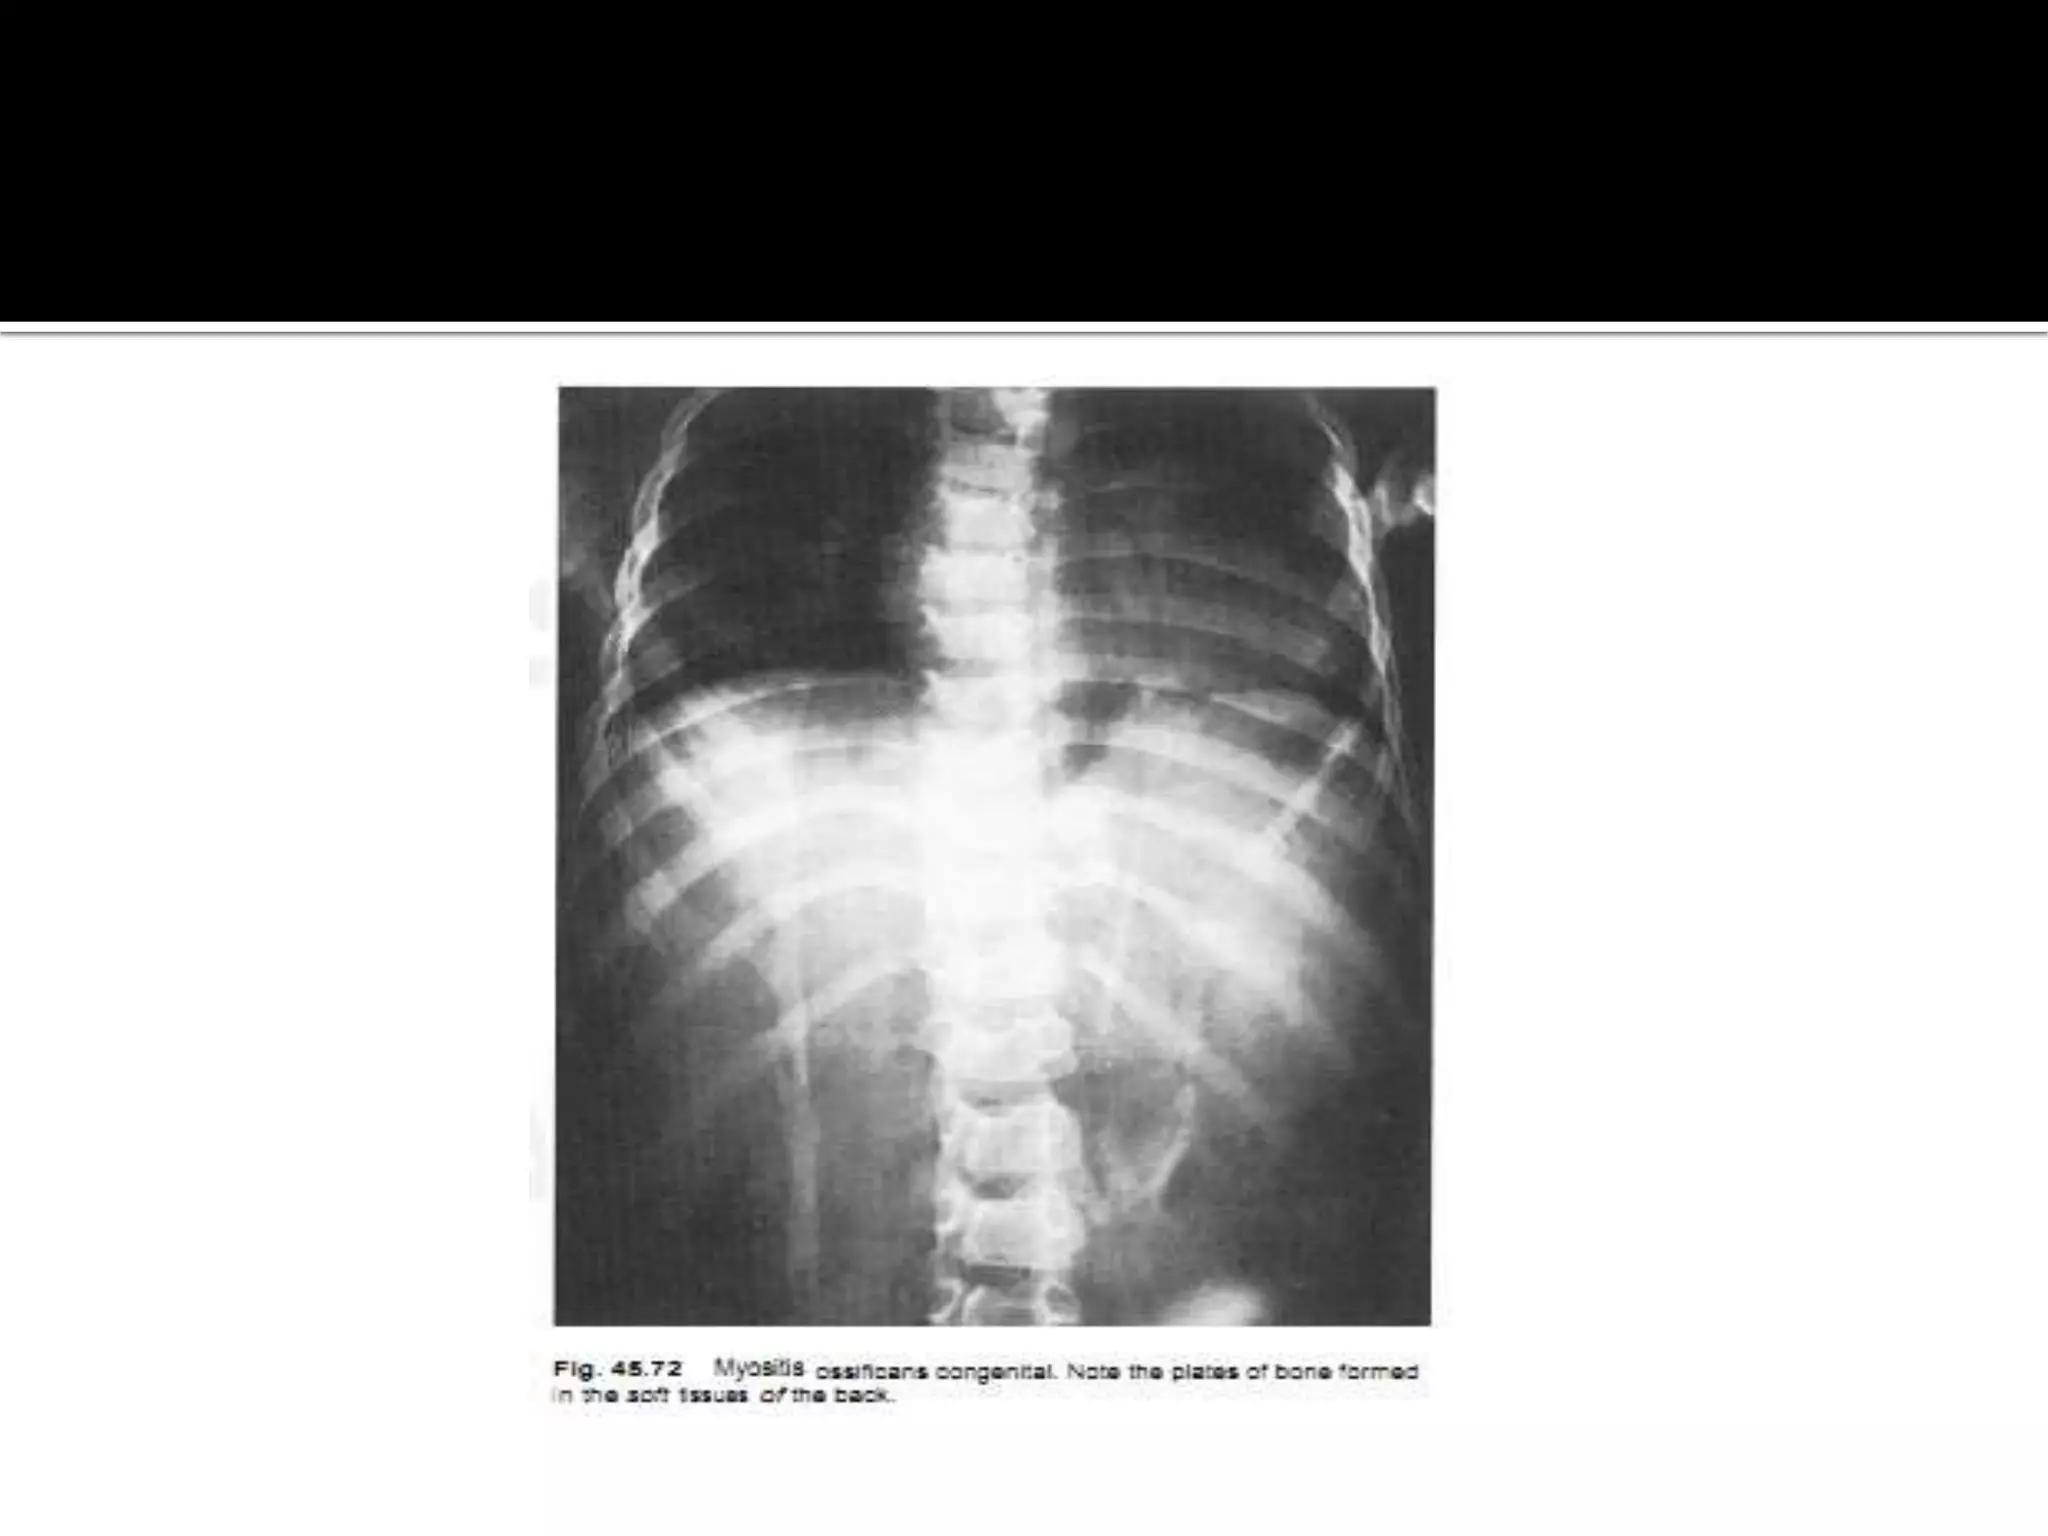

Myocitis osificans progressiva.

 the progressive form myocitis ossificans is a

hereditary disease commoner in boys.

 it presents with ossification of the perimuscular

fascia within one year and is associated with many

congenital bone lesions such as phalangeal and

metacarpalhypoplasia of the thumbs and big toes .

 the condition is usually fatal.

• 42.

Myocitis osificans progressiva. the progressive form myocitis ossificans is a hereditary disease commoner in boys.  it presents with ossification of the perimuscular fascia within one year and is associated with many congenital bone lesions such as phalangeal and metacarpalhypoplasia of the thumbs and big toes .

• 44.

 the conditionis usually fatal.  in the limbs the appearance needs to be distinguished from parosteal sarcoma.